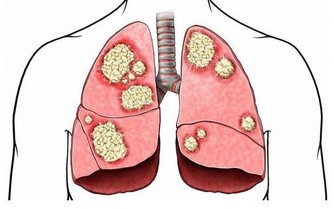

- 穩定清潔功能:不斷清除衰老死亡的細胞,保持體內的淨化更新。

- 監控功能:及時識別和清除染色體畸變或基因突變的細胞,防止癌瘤的發生。

硒是人體不可或缺的微量元素,幾乎存在於所有免疫細胞中。一旦缺乏,會導致免疫力下降,甚至增加癌症風險。